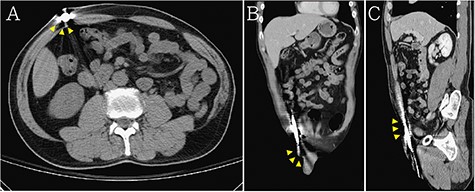

Abdominal CT demonstrated that the penetration extended from the left scrotum to the right anterior abdomen wall (the steel bar: yellow arrow head) in (A) axial view, (B) coronal view and (C) sagittal view.